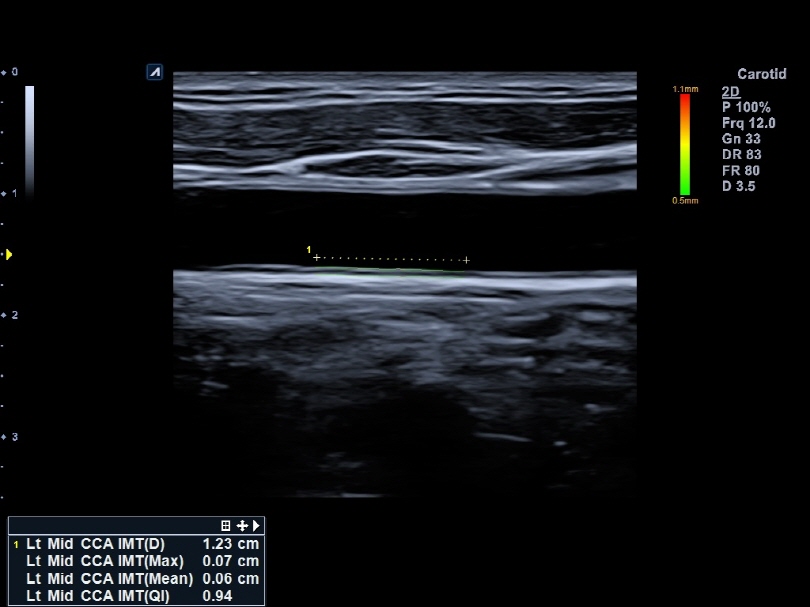

L8-17H

High density linear transducer(8-17MHz)

Application:

Breast, EM, MSK, Vascular, Small Parts

L3-12H

High density linear transducer (3-12MHz)

Application:

Breast, EM, MSK, Vascular, Small Parts

L3-12HWD

High density wide footprint linear transducer (3-12MHz)

Application:

Breast, EM, MSK, Vascular, Small Parts, Appendix

L3-12T

Linear transducer (3-12MHz)

Application:

Breast, EM, MSK, Vascular, Small Parts, Appendix